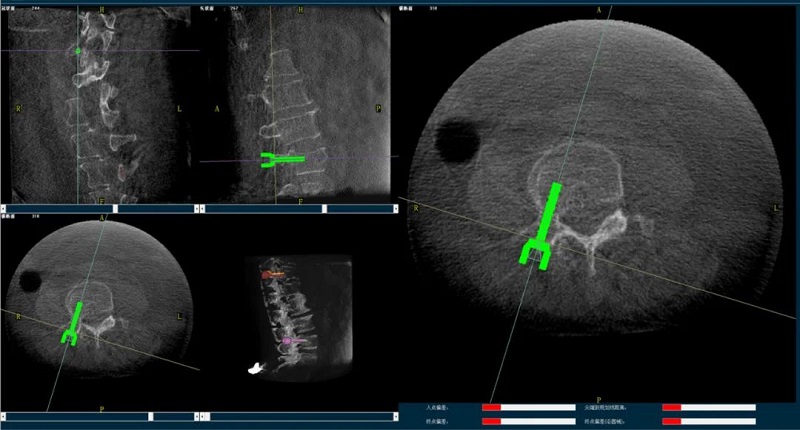

(1)首先使用普愛醫療三維C形臂采集胸腰椎病灶三維圖像,對傷椎進行三維重建;

(2)醫生制定個性化的手術方案,在機器人導航界面上進行路徑規劃;